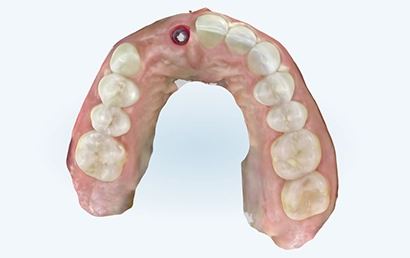

iTero scan taken immediately after implant placement.

Clinically made custom abutment